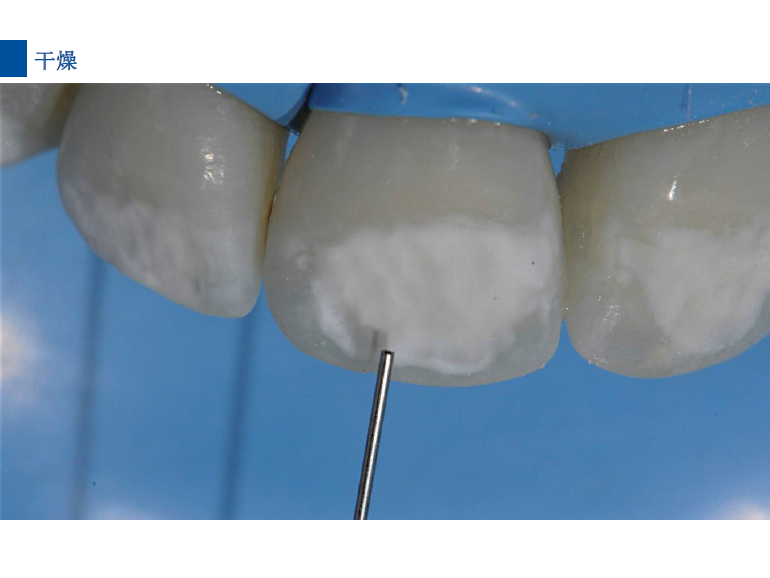

5、 将配套注射头装在含有爱康干燥剂Icon-Dry的注射器上,并将注射器内一半的材料注入龋损部位,等待30秒,吹干。

4、冲洗爱康酸蚀剂Icon-Etch30秒,吹干

5、将配套注射头装在含爱康干燥剂Icon-Dry的注射器之上,将一半的材料涂布于龋损区,等待30s,吹干